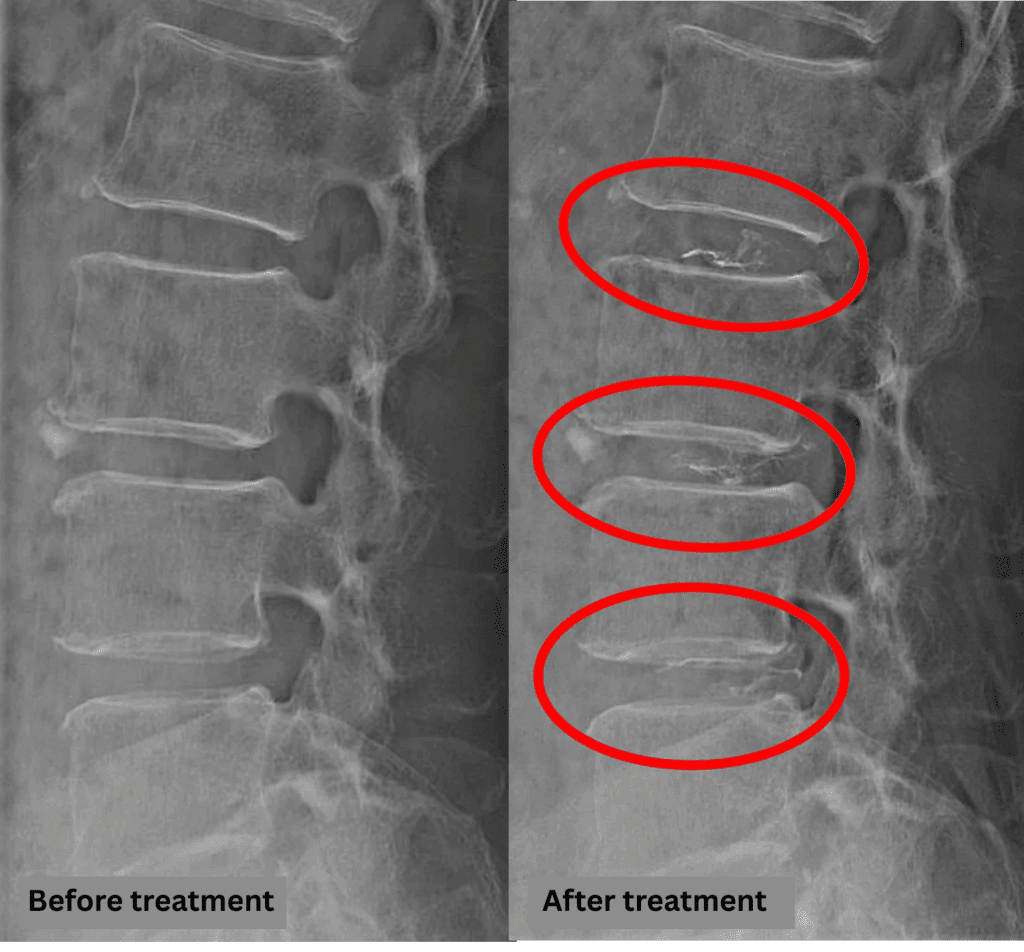

- L2/3, L3/4, L4/5: Disc degeneration, disc herniation, annular tear

These findings indicate compression of the spinal canal caused by disc pathology at L2/3, L3/4, and L4/5, which is likely responsible for the patient’s symptoms.

After consulting with the patient, the Cellgel Method was performed on L2/3, 3/4 and 4/5.